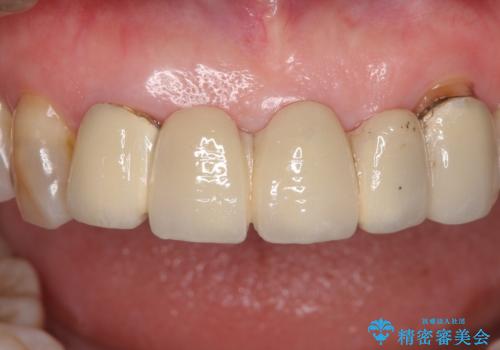

- アンバランスな色や形、歯肉ラインの黒い縁が目立ってしまったブリッジの作り直しを希望して来院された患者様です。

自然な仕上がりとするため、金属を使用しないオールセラミックブリッジにより補綴治療を行うこととしました。

装着されていたブリッジは、支台となっている歯と欠損している歯で色が大きく異なっていましたが、オールセラミックとしたことで、全体的に色調の整った仕上がりとなりました。